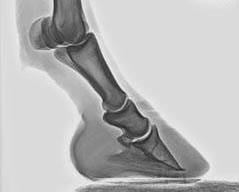

Rehehuf